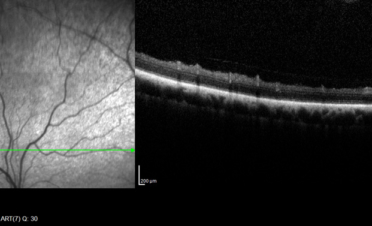

Ante la sospecha de un problema en el segmento posterior del ojo se recomendó la realización de pruebas adicionales que permitieran determinar la causa de su pérdida de visión:

En la angiografía fluoresceínica se apreció hiperfluorescencia del nervio óptico y en la periferia de la retina. Estas imágenes son compatibles con neuritis óptica y coriorretinitis.